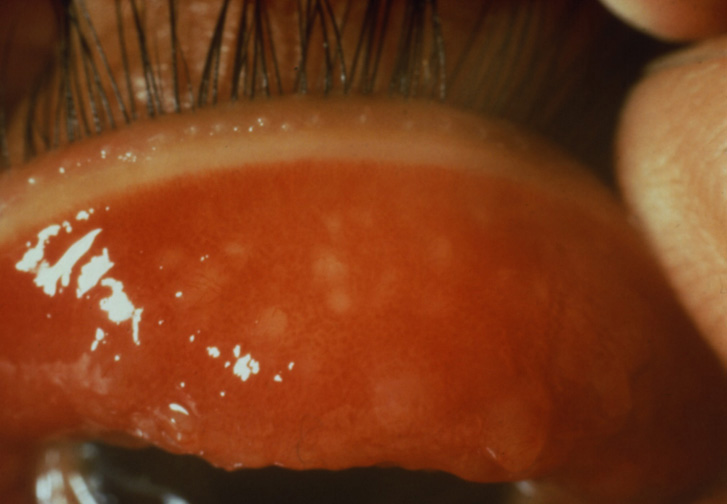

เยื่อบุตาอักเสบจากภูมิแพ้ |